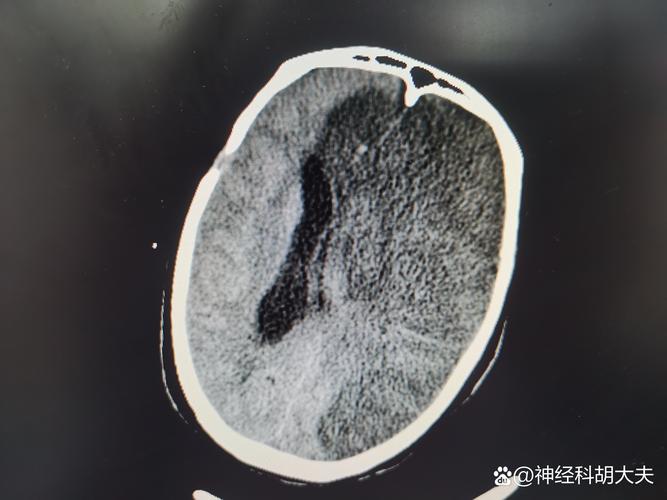

- 脑CT平扫:这是脑梗患者最常做的检查,它主要是通过X射线观察脑组织是否有出血、梗塞、肿瘤等结构性病变,这个检查过程不需要注射造影剂,因此没有空腹的必要。